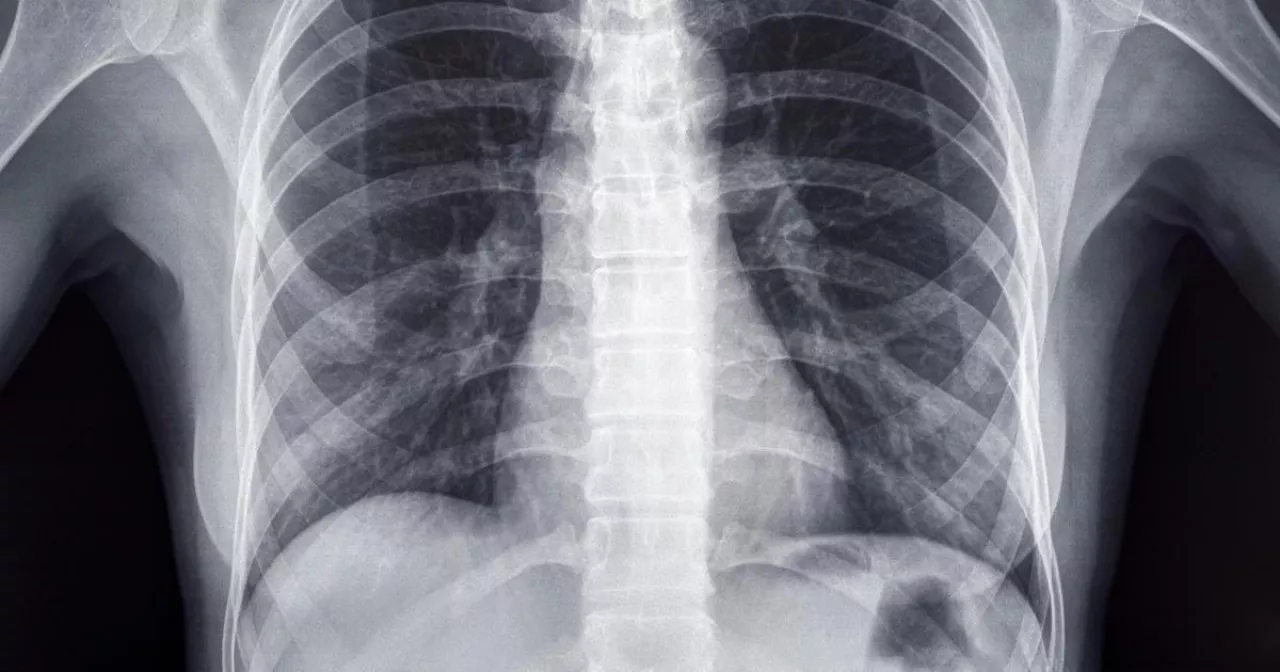

Dijagnoza – rak pluća

Dijagnoza: rak pluća, stadijum 1B, u donjem levom režnju. Kada vam neko izgovori te reči, vreme na trenutak stane. U mojoj glavi odzvanjalo je sve osim lekarevih reči. Sećanja, slike, pitanja, ali najviše osećaj bespomoćnosti. Gledao sam doktora kako pomno objašnjava situaciju i mogućnosti, ali suštinski – ponudio mi je samo jednu opciju: operaciju.